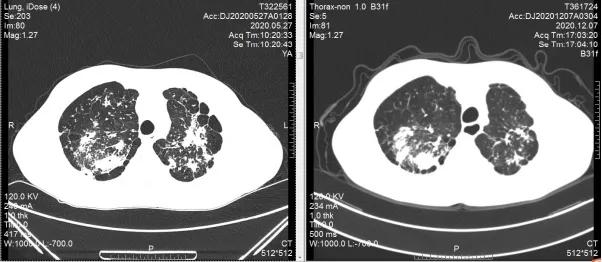

治疗12周复查胸部CT,双上肺部结核病灶较前较少,左下肺部肿瘤较前无大变化,肿瘤评估:稳定,但未再进展。抗痨治疗/抗肿瘤治疗期间,患者耐受性较好,无明显毒副反应,精神状态较前好转,咳嗽、咳痰症状明显减轻,痰涂转阴,极大增加了进一步治疗的信心。继续按原治疗方案行抗痨、抗肿瘤治疗,患者一般状况进一步好转,咳嗽/咳痰症状消失,24周复查胸部CT,双上肺结核病灶部分钙化,病情趋于稳定并向好的方向转归。左下肺肿瘤较前稍增大,肿瘤评估:稳定。

双上肺结核,抗痨治疗24周后病灶较前明显吸收(肺窗)